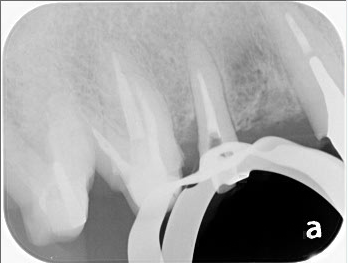

レントゲン上で左から2番目の歯の根管治療を行いました。

治療前は根の先に黒い像が確認できますが、治療後にはかなり縮小しているのが確認できました。